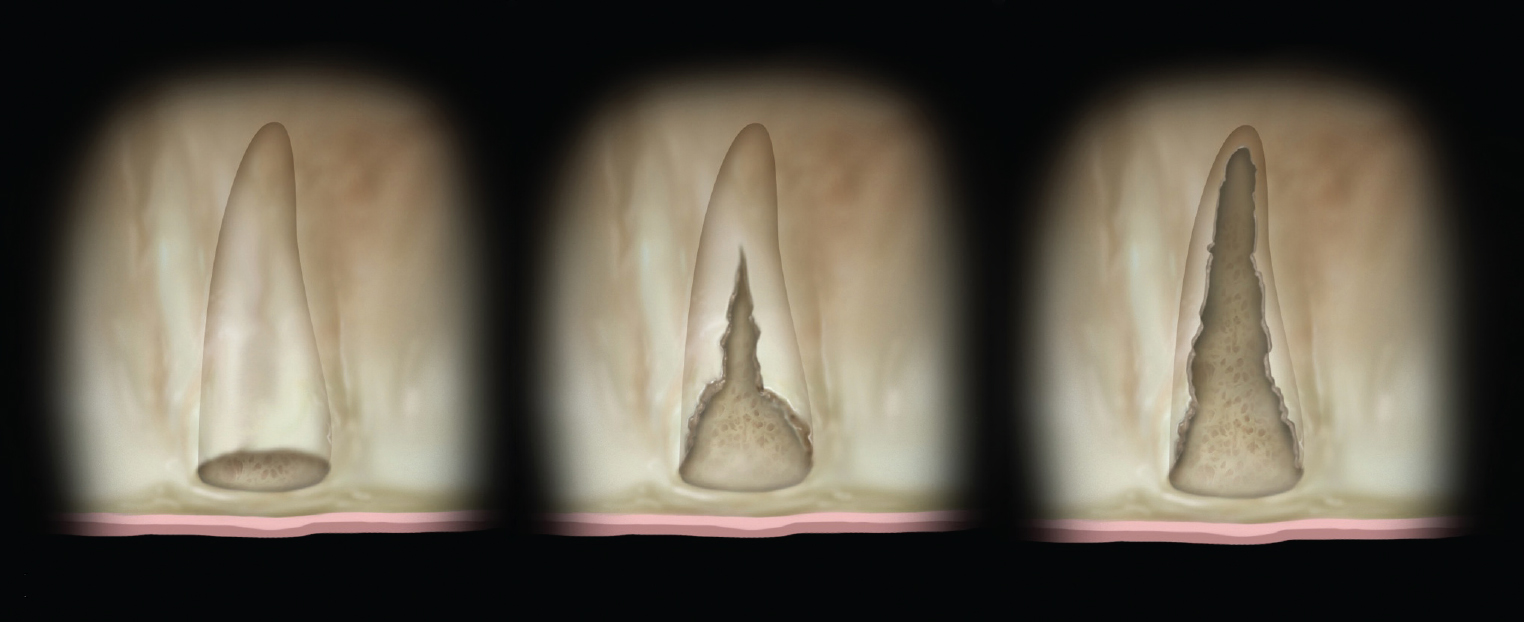

The shape and amount of bone present apical to the extraction socket is the apical topography and is important in treatment planning for both immediate and delayed implant placement. For immediate implant placement, the apical topography is significant, as 3 mm to 4 mm of native bone needs to be engaged for primary stability of the implant.1,2 If planning a 2-stage approach with site preservation and delayed implant placement, analysis of the apical topography is also essential. If a tooth with an apical concavity is extracted and a graft is placed only inside the socket, there may not be adequate bone following healing to place the implant in the proper position without additional surgical procedures3 (Figure 2). Teeth that do not have enough apical bone to provide the housing necessary for immediate implant placement or delayed implant placement with grafting inside the socket alone are defined as having inadequate apical topography. This inadequacy can be the result of periapical pathologies or the anatomy of the alveolus.

Grade I sockets are the most ideal. Following tooth extraction, a socket that has an intact buccal plate, adequate interproximal bone, and satisfactory apical topography will fall into this category. In this classification, an intact buccal plate is defined as having no fissures or dehiscences and less than 25% loss of height (Figure 4, left; Figure 5, left). This percentage of buccal plate loss was selected as the cutoff based on the average root length of single-rooted teeth, which is 14.2 mm,25 and the amount of buccal plate that can be reliably regenerated during immediate implant placement. Adequate apical topography is defined as enough bone present apical to the extraction site to allow for engagement of 3 mm to 4 mm of a properly positioned immediate dental implant (Figure 2).1,2 Adequate interproximal bone is defined as no or mild (up to 2 mm) periodontal bone loss on the adjacent teeth as to allow for support of the interproximal soft tissue and to enable placement of the platform of an immediate implant in the proper apical-coronal position relative to the adjacent teeth while still being bordered by bony walls on the mesial and distal aspects26 (Figure 3, left).

Grade III sockets are the most deficient and include any socket with inadequate apical topography, insufficient interproximal bone, or more than 50% loss of buccal plate. Inadequate apical topography is defined as not enough bone present apical to the extraction site to allow for implant placement and may be the result of bone loss caused by periapical lesions or concavities due to existing anatomy of the alveolus (Figure 4, right; Figure 5, right). Insufficient interproximal bone is defined as moderate-to-severe periodontal bone loss—greater than 2 mm on one or both of the adjacent teeth.